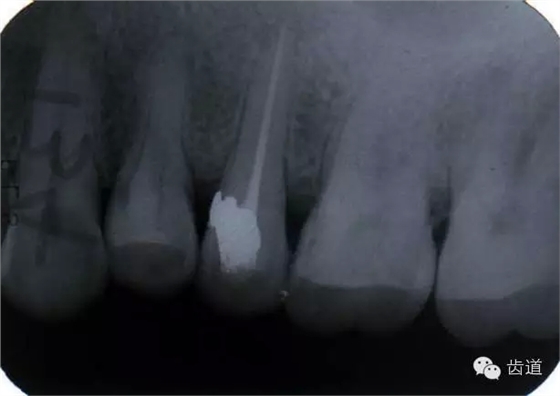

左上5牙頸部側(cè)穿

左上4鑄造樁側(cè)穿